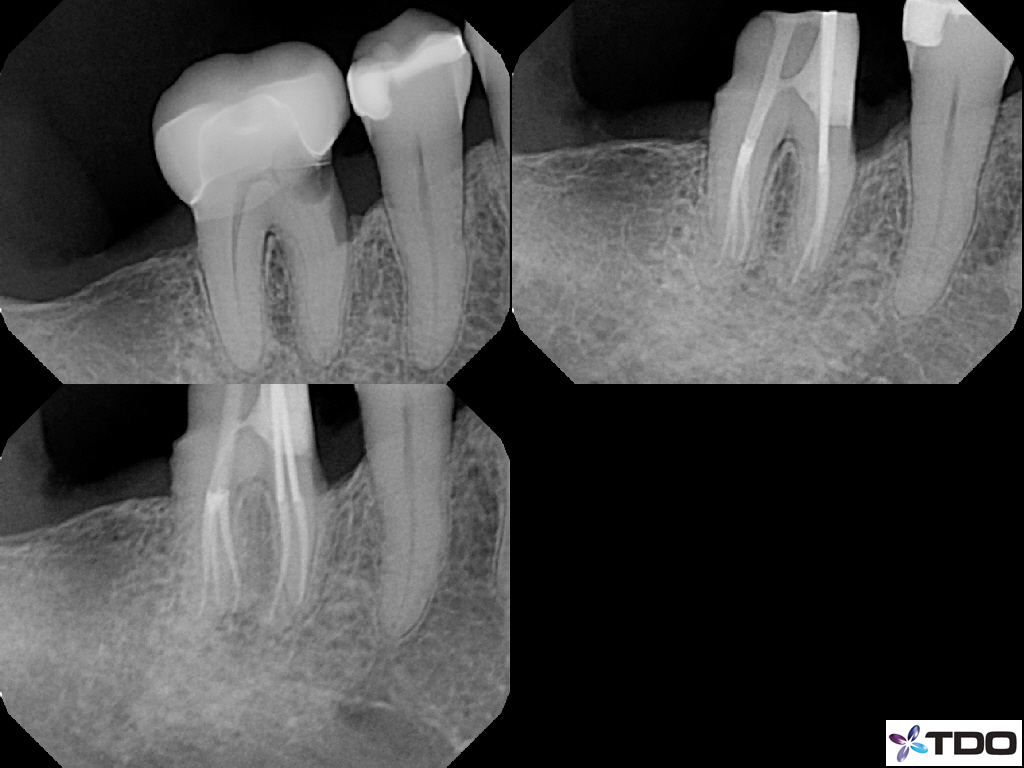

These cases show a level of commitment to conservative endodontics rarely seen in endo today. Plus the restorative excellence is inspiring and should stimulate all endodontists to up their game and help others realize how important the restorative aspect of endodontics is.